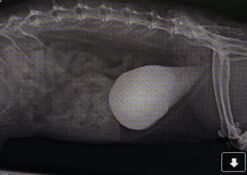

- Rabbitats. (2019). Munch's x-ray with bladder and urethra stones and a herniated bladder